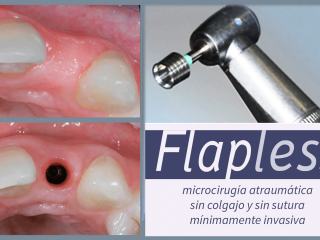

SOFT TISSUE INTEGRATION, IMMEDIATE FUNCTION & FLAPLESS

En este sentido nuestro consultorio desarrolla desde 1999 la técnica flapless prescindiendo del bisturí convencional y sin sutura, a través de una incisión circular de 5 mm de diámetro que garantiza un postoperatorio que pasa inadvertido y logra excelente resultado estético.

La técnica quirúrgica flapless (sin solapa) posee varias ventajas comparada con los procedimientos quirúrgicos convencionales, que incluyen la apertura de una solapa (flap) antes de la inserción del implante.